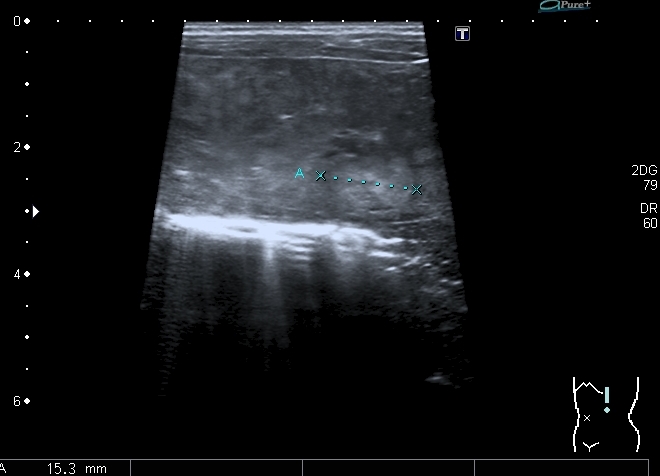

Правый надпочечник представлен округлым гиперэхогенным тканевым образованием с участками кальцификации, гиповаскулярным по отношению к ткани печени и почки

Моё заключение: нейробластома правого надпочечника с тотальным метастатическим поражением печени. Прошу членов форума высказать своё мнение о случае. Постараюсь отследить верификацию.

Верифицированный морфологически диагноз: С74.9 Низкодифференцированная нейробластома правого надпочечника с метастатическим поражением печени и костного мозга. T2N0M1, IVS стадия.